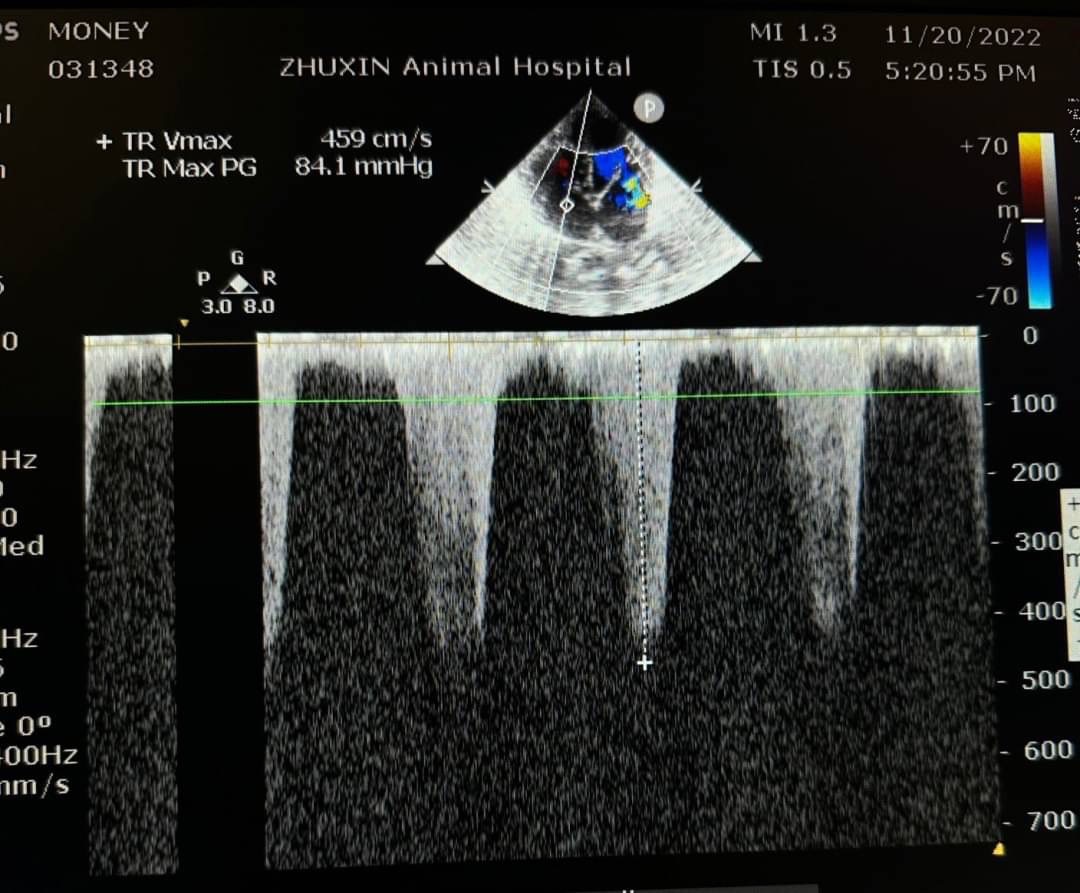

腹腔超音波下出現腹水,肝臟腫大伴隨肝門靜脈擴張。腹水檢測為漏出液,抹片下為少量發炎細胞,並無看到細菌。針對X光下心臟變大的影像,安排後續心臟超音波檢查,診斷為肺部高壓誘發肝門靜脈壓力上升引發腹水出現。心電圖下並無明顯心律不整。

而一般常使用心臟超音波參數和結構回推肺部壓力是否過大

如測量肺動脈或是三尖瓣逆流的流數,心臟結構的改變,如右心房擴張、右心室肥厚、收縮期中隔平坦、肺動脈擴張(PA:AO >1)等。